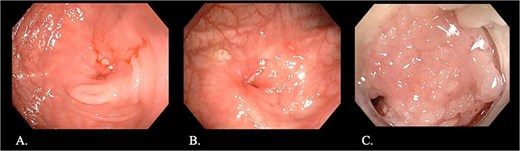

CT enterography demonstrated strictures involving the third and fourth portions of the duodenum with proximal gastric dilatation (Fig. 1), inflammatory changes in the transverse colon mesentery, and thickening of the neoterminal ileum (Fig. 2). Push enteroscopy confirmed a non-traversable stricture with multiple ulcers in the third portion of the duodenum; biopsies indicated chronic duodenitis. Colonoscopy revealed a non-traversable stricture at the ileocolic anastomosis, with biopsies showing severely active chronic enteritis (Fig. 3).

Endoscopic images: (A, B) Stricture at the ileocolic anastomosis with severely inflamed mucosa (arrows). (C) Non-traversable duodenal stricture observed during push enteroscopy.